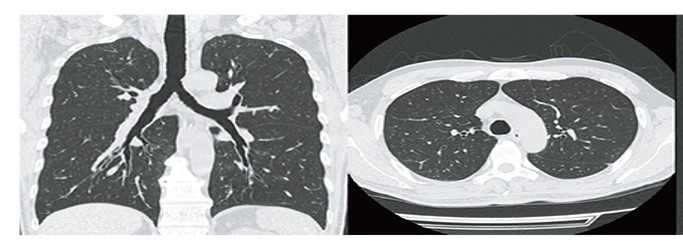

肺と胸部のCT画像

肺の画像。空気があるため黒く見える/ 胸部の画像。骨は白く、脂肪は灰色に見える